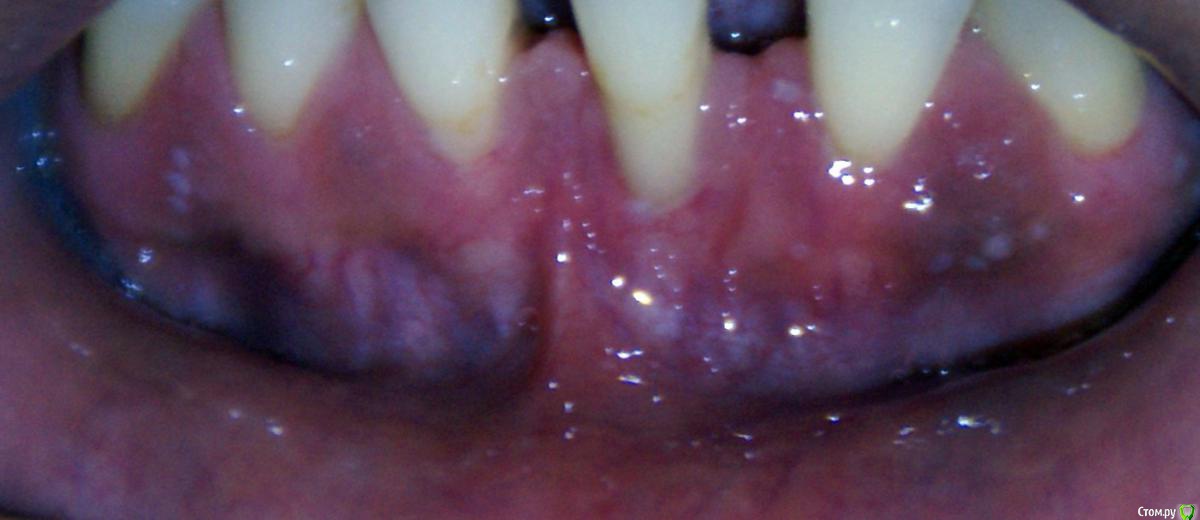

Irina_S Опубликовано 22 июня, 2017 Автор Поделиться Опубликовано 22 июня, 2017 Преддверие увеличилось достаточно.Как мне измерить это увеличение? Я не вижу разницы. Было:Стало:Вижу только отсутствие уздечки по центру. А по сторонам стало даже выше. И рубцы-тяжи влияют на дёсны около клыков. Ссылка на комментарий

Irina_S Опубликовано 26 июня, 2017 Автор Поделиться Опубликовано 26 июня, 2017 Спасибо всем за ответы! Рана меньше - это, с одной стороны, хорошо, конечно. Но мне кажется, что именно из-за уменьшения длины разреза возникла чрезмерная натянутость, которой не было до операции. И когда я массирую давящими движениями вниз, то вижу, как натягиваются и белеют рубцы и оттягивают дёсны почти под всеми зубами. На сегодняшний день заметно опускание дёсен по сравнению с ситуацией до операции. Получается, что действиями, которые должны мне помочь в восстановлении, я только делаю хуже? Возможно ли восстановление дёсен, когда пройдёт тот самый неясный по продолжительности период заживления, когда тяжи перестанут тянуть? Как мне правильно поступить, чтобы не ухудшать ситуацию дальше? Если надо всё переделывать, то я готова к этому. Ссылка на комментарий

Bier Опубликовано 26 июня, 2017 Поделиться Опубликовано 26 июня, 2017 нужно наладить гигиену прежде всего, у вас все в камнях и налете. 2 Ссылка на комментарий

Irina_S Опубликовано 27 июня, 2017 Автор Поделиться Опубликовано 27 июня, 2017 нужно наладить гигиену прежде всего, у вас все в камнях и налете.Полностью с Вами согласна! Пункт первый: наладить гигиену. За полгода после чистки успевает вот так накапливаться, видимо из-за состава слюны. Скоро иду в очередной раз.Пункт второй - ? Ссылка на комментарий